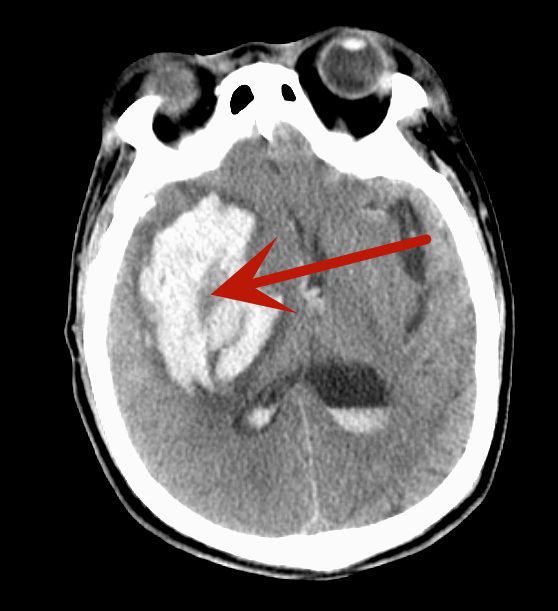

据悉,55岁的赵先生突发脑出血倒在路边,被路人发现时,已经不省人事,呼之不应,伴有呕吐、大小便失禁,被120紧急送至我院。急诊检查CT结果令人揪心:右侧基底节脑出血,右侧脑室受压,中线结构左偏,颅内情况异常凶险,被紧急收至神经外科。

(红色箭头为颅内出血灶)

救治刻不容缓,向患者家属详细讲解手术方案,并征得同意后,手术团队立即为患者实施颅内血肿清除手术。由李自强主任主刀,手术团队凭借丰富的临床经验和精湛的医疗技术,密切配合,精细操作,手术顺利完成。